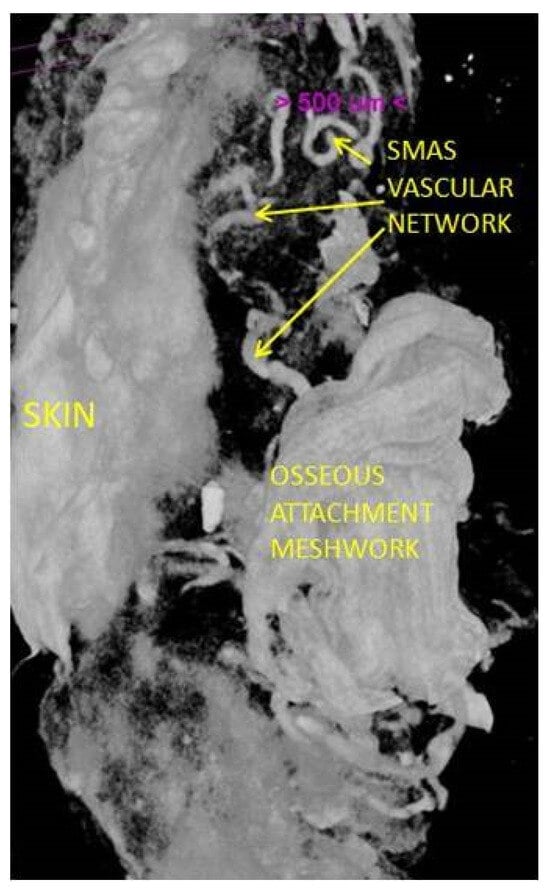

The results of our micro-CT study are consistent with those of IHC stainings. We were able to identify the dermal and subdermal vascular plexuses as well as the communication between them.

In the preauricular area, we found blood vessels that are parallel with the skin within the SMAS thickness (Figure 9 and Figure 10).

The results of the micro-CT study show us the presence of a vascular network inside the SMAS but also provide us details about it [48].

Unlike other vascular territories studied, at the level of the retaining ligaments, the vascular network does not follow any fibrous pathways and is not ensheathed. At the level of each of the studied regions, we found blood vessels with a transversal disposition to the skin, whose existence has not been known until now.

Their tortuous path can indicate that they represent a vascular network specific to the SMAS, and this can form anastomosis with the branches that cross the thickness of the SMAS in a plane perpendicular to the skin.

Figure 10. SMAS fibrous collagen septa crossing to the skin together with muscular fibers; transvers and tortuous blood vessels within SMAS. Preauricular area; specimen after 14 days in Lugol Iodide solution. 7 µm scanning.